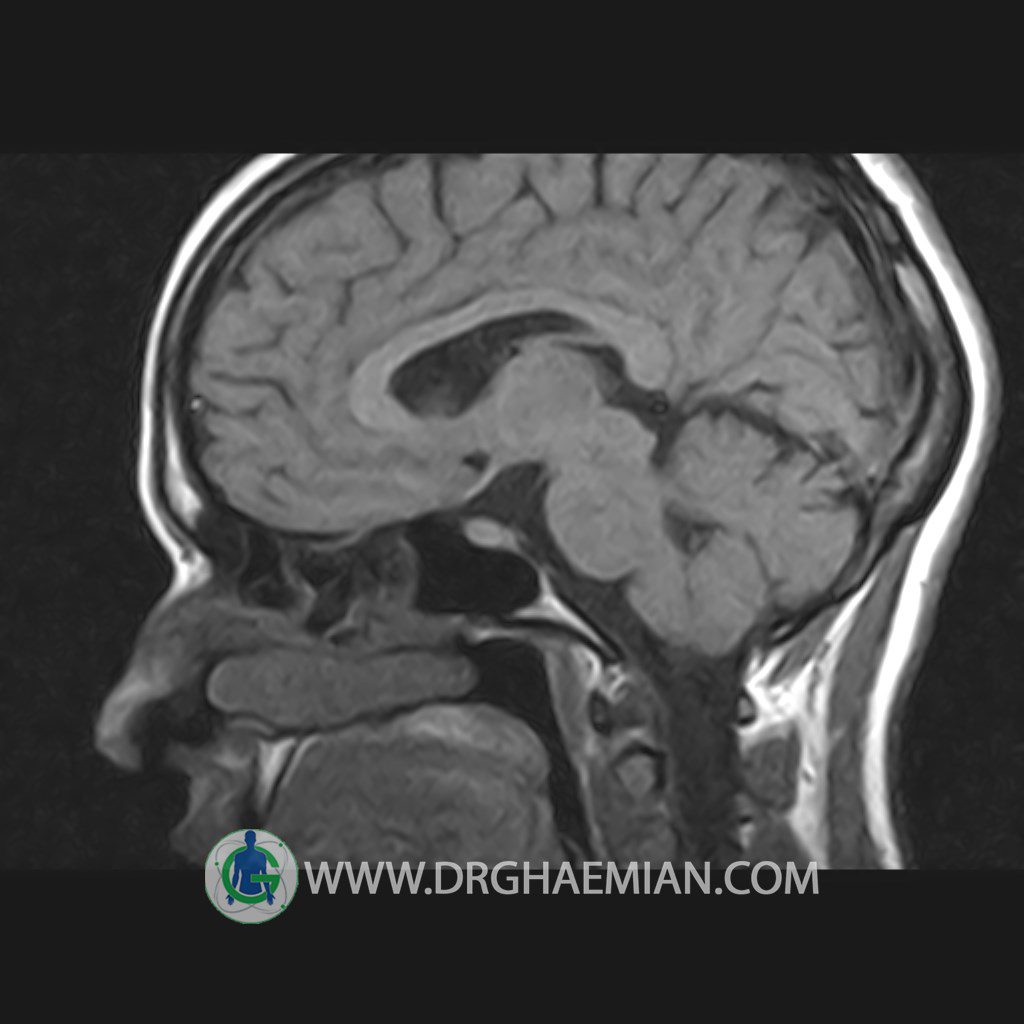

پزشکان اغلب از تصویربرداری ام آر آی برای تشخیص و درمان عارضه های پزشکی که فقط با استفاده از اشعه ایکس یا میدان مغناطیسی و امواج رادیویی قابل مشاهده است، استفاده می کنند. دستگاه ام آر آی تصاویر دقیق از ساختار های داخلی بدن ایجاد می کند. در این کیس هیپرپلازی هیپوفیز و آدنوم مشاهده می شود.

HYPOPHYSIS MRI

(with and without contrast)

Technique: Axial , coronal T1 , Axial , coronal , sagittal T2 , Axial, coronal T1 post Gd & 64 dynamic thin coronal slices.

REPORT :

The sella shows normal size , position and configuration .

The borders of its floor and walls are smooth and sharply defined .

The infundibulum is centered and of normal size .

The optic chiasm and suprasellar spaces appear normal .

The cavernous sinus and imaged portions of the internal carotid artery and carotid siphon are unremarkable .

Evaluable portions of the neurocranium show no abnormalities .

The sphenoid sinus is clear and pneumatized .

– Mild convexity at superior border of pituitary gland with post contrast homogeneous enhancement suggestive for pituitary hyperplasia & iso signal adenoma

is seen